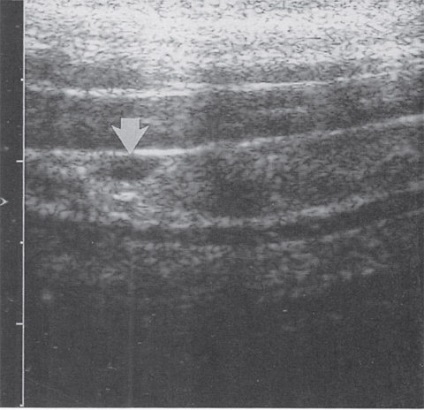

Mellékpajzsmirigy ultrahanggal

A normális állapotban, ezek az endokrin szervek ultrahang jelennek homogén hypoechoic ovális vagy lekerekített sima képződése szempontjából tiszta kontúrokkal, bármilyen mennyiségben legfeljebb 30 mm, amelyek vannak elhelyezve a felső és alsó pólusa a pajzsmirigy hátsó fal. Erezettség mellékpajzsmirigy a legtöbb esetben hiányzik.

A gyakorlatban az ultrahang szakemberek a felmérés a mellékpajzsmirigyei meglehetősen gyakori álnegatív és álpozitív eredmények hasonlósága miatt a megnövekedett glandulae parathyroideae csomós daganatok a pajzsmirigy, található a megfelelő helyeken:

Továbbá, az orvosok néha félreértelmezik normális anatómiai szerkezete, - hosszú nyakizom, a bal oldali fal a nyelőcső. Ugyancsak nem könnyű megkülönböztetni mellékpajzsmirigyben a nyirokcsomók, amelyek lokalizált ugyanazokra a helyekre.